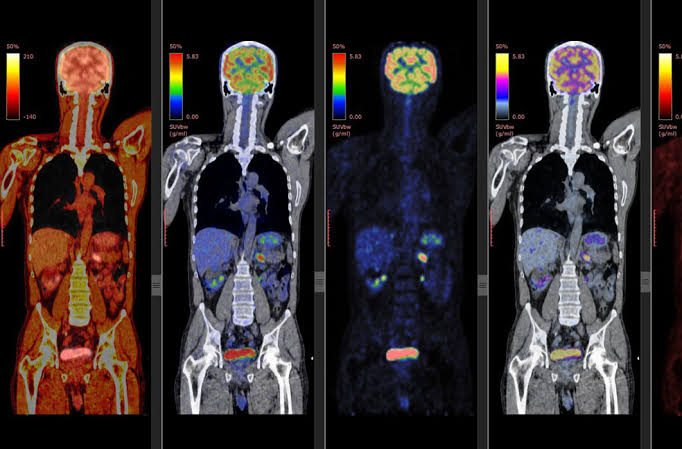

PET-CT scan

Positron emission tomography (PET) uses small amounts of radioactive materials called radiotracers or radiopharmaceuticals, a special camera and a computer to evaluate organ and tissue functions. By identifying changes at the cellular level, PET may detect the early onset of disease before other imaging tests can.

For some types of cancer, a PET-CT scan is a way to help find cancer and learn its stage. Stage is a way to describe where the cancer is and if it has spread. Doctors also learn information about the stage if and how the cancer is affecting your body's functions.